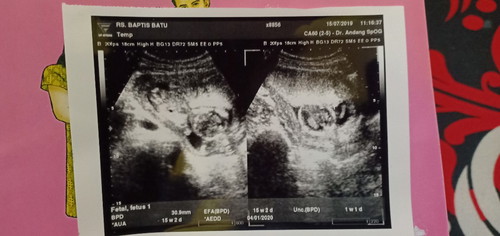

Uk USG & uk hitungan dari HPHT berbeda 1w4d

Bund mau tanya, apa memang selalu uk perhitungan dari HPHT berbeda dari uk USG? Ini td suamiku kaget, dihitungan dari HPHT udh 16w6d tp di USG masih 15w2d. Sampe khawatir sendiri mikir kalo janinku perkembangannya agak lambat grgr bulan ini aku kebanyakan nurutin ngidam yg terbilang ga sehat☹️ . Tp Alhamdulillah, kata dokter sehat. Nantinya apa akan selalu beda gitu ya bun?